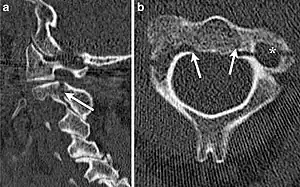

| CT scan of hangman's fracture | |